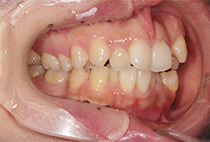

出っ歯と前歯のガタつきにお悩みだった20代女性の症例です。

前歯のガタガタ、中心のずれ、顎のずれ、外科矯正は避けたい

叢生、左右非対称咬合